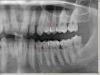

soft Опубликовано 19 января, 2010 Поделиться Опубликовано 19 января, 2010 (изменено) Здравствуйте.Пару лет назад поставили пломбы между нижними 6 и 7. Сейчас снова появилась боль в этом месте. Решил сделать ортопантомограмму, прежде чем сдаваться врачам, так как в прошлый раз лечили совсем без рентгена и, есть мнение, что не долечили. Прокомментируйте, пожалуйста, что видно на снимке. И что стоит делать дальше. Обзорный снимокУвеличенные левая и правая часть Update: Речь идет о 6-7 зубах с противоположной стороны от коронки. Изменено 19 января, 2010 пользователем soft Ссылка на комментарий

annda Опубликовано 19 января, 2010 Поделиться Опубликовано 19 января, 2010 (изменено) Здравствуйте.Пару лет назад поставили пломбы между нижними 6 и 7. Сейчас снова появилась боль в этом месте. Решил сделать ортопантомограмму, прежде чем сдаваться врачам, так как в прошлый раз лечили совсем без рентгена и, есть мнение, что не долечили. Прокомментируйте, пожалуйста, что видно на снимке. И что стоит делать дальше. Обзорный снимокУвеличенные левая и правая частьжелательно подробное описание боли(постоянство или периодичность,если приступы.то как долго,с чем связаны,отдаёт ли в соседние зубы,ночные или дневные) и фото во рту(не могу понять,что за конструкция,коронку вижу ,а вот что в 5ке,так и не могу понять,как будто монолит с коронкой на 6м).Каналы не самые худшие,что тут показывали,но и не высокий образец эндодонтического ремесла.Всё зависит-как болит. Изменено 19 января, 2010 пользователем annda Ссылка на комментарий

annda Опубликовано 20 января, 2010 Поделиться Опубликовано 20 января, 2010 Я видимо плохо объяснил, но речь шла о 6-7 с другой стороны. Зуб под коронкой не беспокоит.Периодическая боль появилась несколько месяцев назад при жевании. Последнюю неделю это место стало еще более чуствительным, один раз при жевании была резкая боль.Надо заметить, что это место у меня очень чуствительное. Когда ставили там пломбы, то была боль даже после двух шприцов анестезии.Там неважная (по снимку!) пломба в 7ке. Ссылка на комментарий

Мартовский Опубликовано 20 января, 2010 Поделиться Опубликовано 20 января, 2010 Там неважная (по снимку!) пломба в 7ке.По снимку - да, а на самом деле может и нет, может там прокладка из сиц нерентгенконтрастная, сделаем такой допуск. Но конечно в первую очередь я бы обратил внимание на неё. Ссылка на комментарий